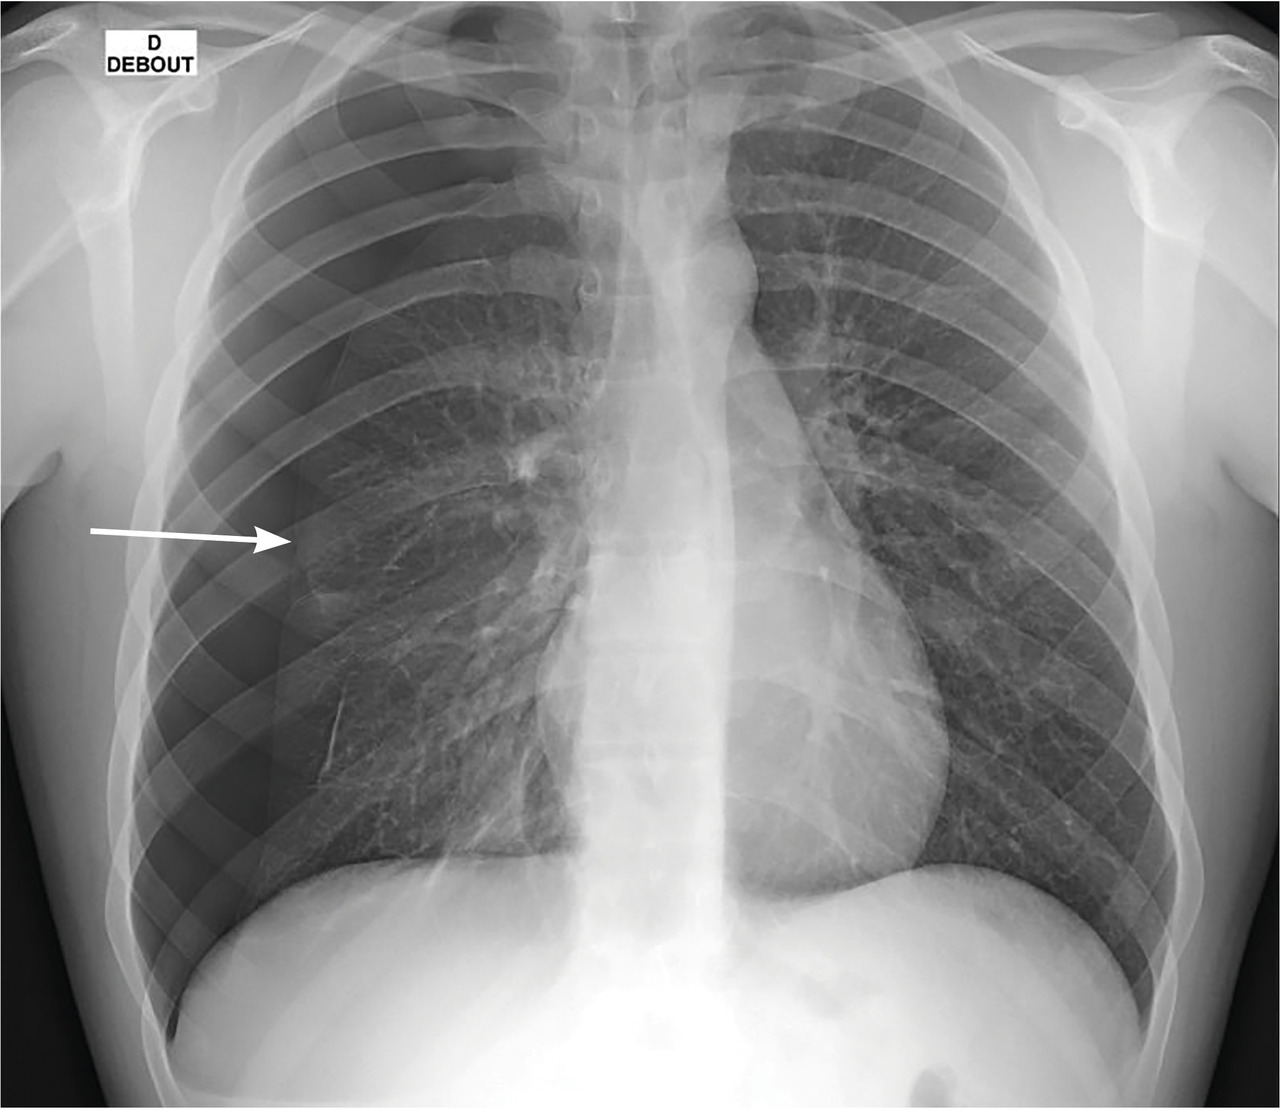

à la radiographie thoracique(de face, debout et en inspiration ; clichés en expiration non recommandés) :

– hyperclarté avasculaire plus ou mois importante délimitée en dedans par la plèvre viscérale visualisée par une ligne bordante pleurale ;

– pneumothorax dit « complet » en cas de décollement sur toute la longueur de la ligne axillaire de l’apex au diaphragme ;

– on recherche des signes de compression avec déviation médiastinale et refoulement des organes, une bride retenant partiellement le poumon à la paroi (sa rupture peut provoquer un hémopneumothorax) ;

– on peut estimer la taille : pneumothorax de grande abondance défini par un décollement à l’apex de plus de 3 cm (pour l’

) et/ou de plus de 2 cm au niveau du hile (selon la

).